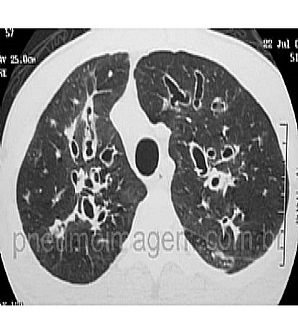

NOVO GUIDELINE SOBRE ATUALIZAÇÃO E CONTROLE DE INFECÇÕES EM FIBROSE CÍSTICA: FAÇA O DOWNLOAD.A Cystic Fibrosis Foundation encomendou uma atualização sobre o controle e prevenção das infecções em Fibrose Cística (FC), que foi publicada neste mês de agosto (Infection Prevention and Control Guideline for Cystic Fibrosis: 2013 Update).

Essa atualização surgiu pela necessidade de integrar as recomendações de diretrizes baseadas em evidências publicadas desde 2003 em práticas de controle e prevenção de infecções em FC, pelo maior entendimento sobre a transmissão por gotículas dos patógenos respiratórios na população não-CF e pela maior compreensão da epidemiologia dos mais recentes patógenos que estão aumentando em prevalência e estão associados ao aumento da morbidade e mortalidade na FC. Tais patógenos incluem S. aureus MRSA, Mycobacterium abscessus, novas espécies no Burkholderia cepacia (por exemplo, Burkholderia dolosa ) e clones epidêmicos de Pseudomonas aeruginosa (por exemplo, a epidemia de deformação Liverpool).